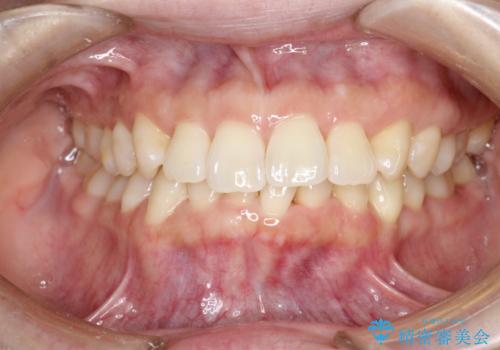

インビザライン ライトパッケージによる部分矯正治療 下の前歯のみの歯並び改善

- インビザライン ライトパッケージパーシャル(下顎のみ)

- 下の前歯の歯並びのみの改善をご希望されました。

インビザライン ライトパッケージ下顎のみ(1枚~14枚まで)での治療を行なっていきました。

マウスピース枚数 初回14枚 + 追加13枚

概ね7ヶ月で治療完了しました。

インビザラインのライトパッケージでは14枚までという枚数制限がありますが、限られた枚数の中で当院独自の工夫を随所に盛り込み、狙い通りの治療結果が得られました。